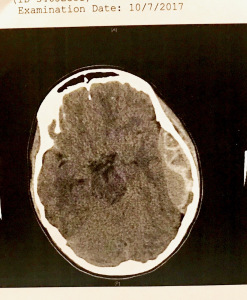

I looked at him, then to the monitor and my husband pointed out the gray blob on the image of our son’s brain, which shouldn’t be there.

“It’s a bleed,” he said.